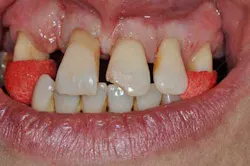

Fig. 2: Anterior teeth relationships prior to treatment

Diagnosis

The patient’s main problem is adult aggressive periodontitis, aggravated by tobacco use. The consequent tooth losses have caused migrations of the remaining teeth under functional adaptation.